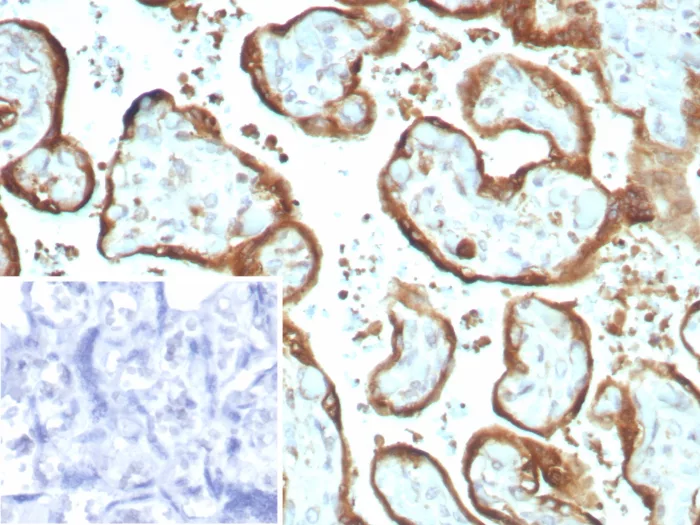

Formalin-fixed, paraffin-embedded human placenta stained with IMP-3 Recombinant Rabbit Monoclonal Antibody (IMP3/8934R) Inset: PBS instead of primary antibody; secondary only negative control.